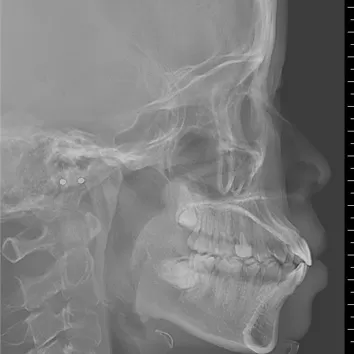

Rayons X avant le traitement

[Radiographie panoramique/Céphalogramme latéral]